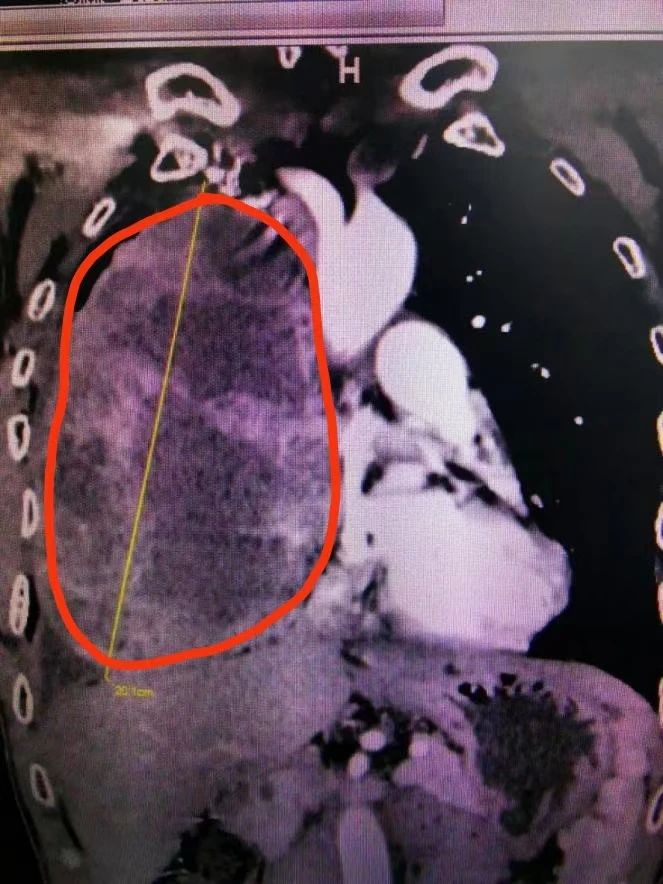

近日,重庆医科大学附属璧山医院(重庆市璧山人民医院)胸心血管外科成功开展一项剖胸探查术+纵隔肿瘤切除术+心包部分切除术,为患者摘除一颗直径近20厘米、体积有“足球”大小的肿瘤。这一项手术的成功完成不仅为患者解决了疾病的困扰,也展现了我院处理胸心外科领域疑难杂症的高超技术。